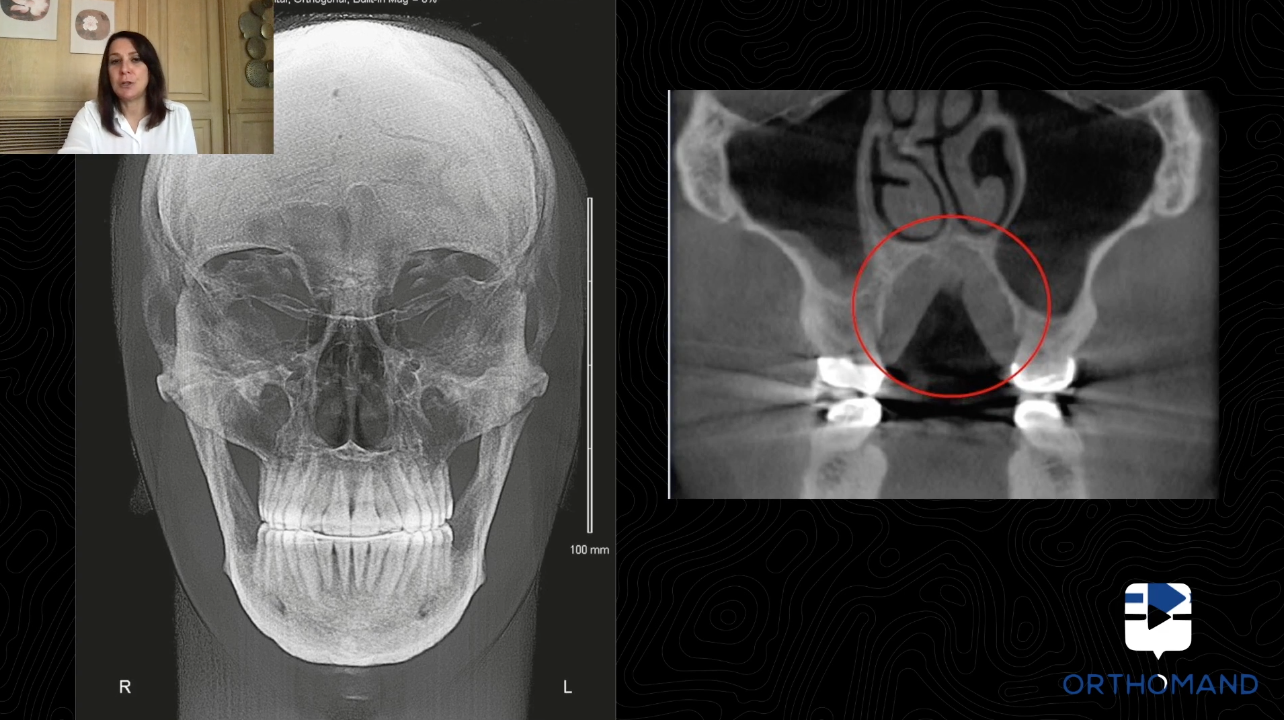

Estratti dal corso